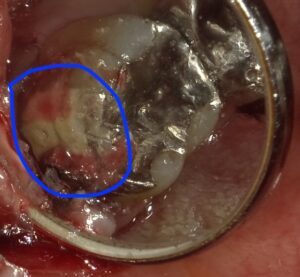

縫合を終えたところです。

被せ物の中にセメントが埋まっているのがわかります。